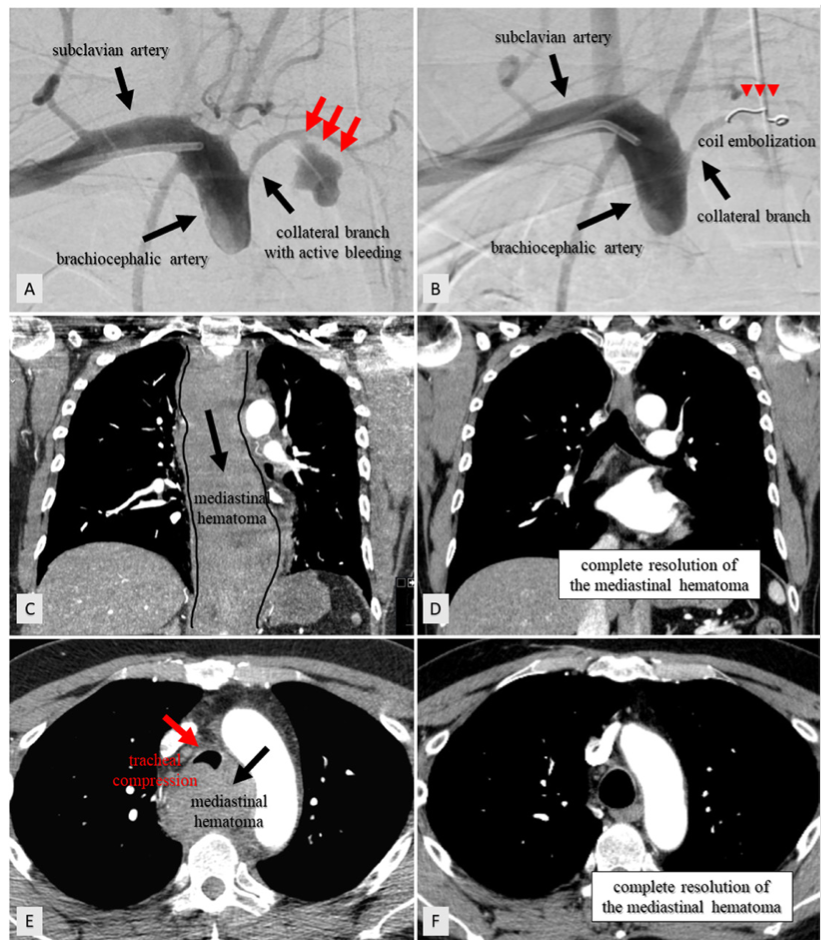

Coil Embolization for Management of Brachiocephalic Artery Perforation Coil Embolization Of Hematoma Embolization of the middle meningeal artery (mma) has emerged as a minimally invasive means of managing. embolization procedures for extracranial disease in the head and neck region are mostly performed for intractable epistaxis. middle meningeal artery embolization (mmae) has shown promise as an alternative treatment for chronic. sometimes coils are used with stents to prevent the coils. Coil Embolization Of Hematoma.